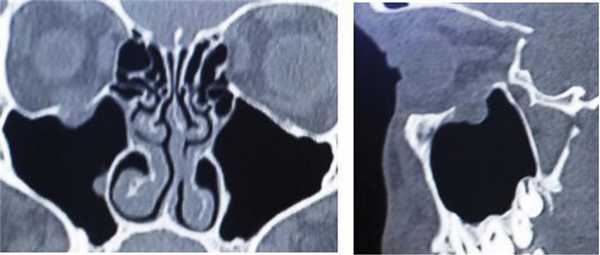

Пациент С., 17 лет, обратился в нейрохирургическое отделение стационара медико-санитарной части «Нефтяник» с жалобами на диплопию, сохраняющуюся в течение 1 мес после тупой травмы глазницы справа. На мультиспиральной компьютерной томографии (МСКТ) околоносовых пазух и орбиты определяется дефект верхней стенки правой ВЧП с пролабированием параорбитальной жировой клетчатки в пазуху (рис. 4). Рис. 4. МСКТ околоносовых пазух и глазницы справа: коронарная и сагиттальная проекции. Дефект нижней стенки правой глазницы (верхней стенки ВЧП) с пролабированием параорбитальной клетчатки. Defect of the lower wall of the right orbit (the upper wall of the maxillary sinus) with the prolapse of the paraorbital adipose tissue into the sinus.

Пациент Ш., 18 лет, обратился в нейрохирургическое отделение стационара медико-санитарной части «Нефтяник» с жалобами на диплопию, сохраняющуюся в течение 2 нед после тупой травмы глазницы справа. На МСКТ околоносовых пазух и орбиты справа определяется дефект верхней стенки ВЧП с пролабированием параорбитальной жировой клетчатки в пазуху (рис. 7). Рис. 7. Пациент Ш., 18 лет. МСКТ. Посттравматический дефект нижней стенки глазницы. Пролабирование параорбитальной клетчатки в просвет ВЧП (указано стрелкой). Prolapse of the paraorbital adipose tissue into the maxillary sinus lumen (indicated by he arrow).